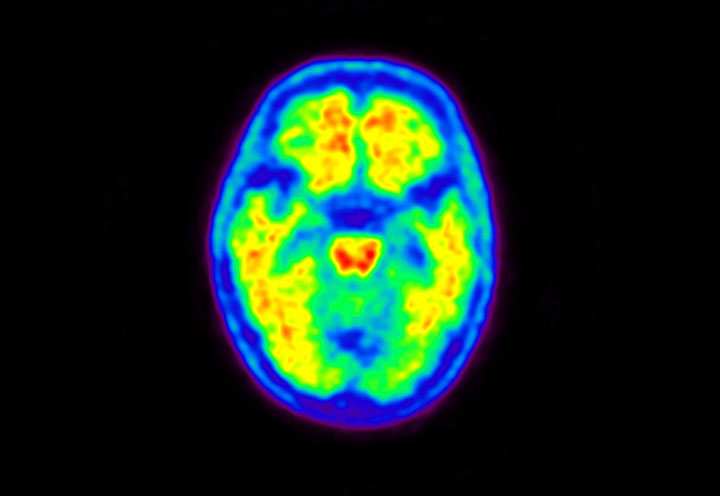

Head / Case5 : Amyloid

Courtesy : Kindai University Hospital

- Imaging protocol

- Injected dose: 4.27 MBq/kg, 18F-Flutemetamol

- Uptake time: 99 minutes

- Scan time: 20 minutes